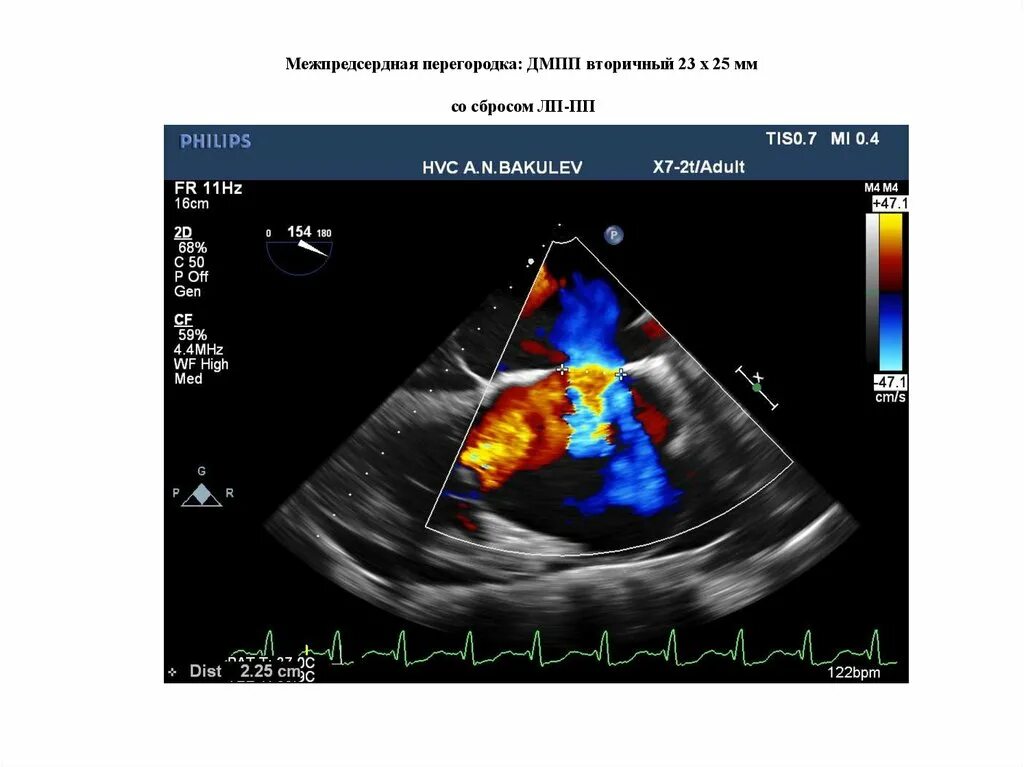

Дефект мпп